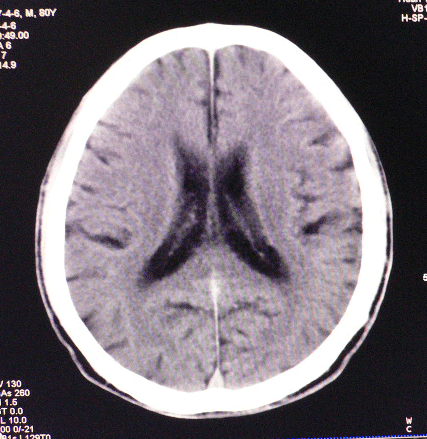

以下是引用狙击手在2007-4-8 22:45:00的发言:[br]出血?从患者的症状考虑病灶应该在左侧大脑半球的基底节区或颞顶部,如此小的病灶引起上述症状的可能性不大,患者可能有梗塞(时间短,目前ct还看不见)或是tia发作,再者像这样的线条形出血的确不多见,但还是有可能的,曾经碰到有外伤类似出血,复查后消失,所以还是慎重一点,短期复查即可。

以下是引用dyqct在2007-4-8 16:25:00的发言:[br]支持左侧放射冠区少量出血。